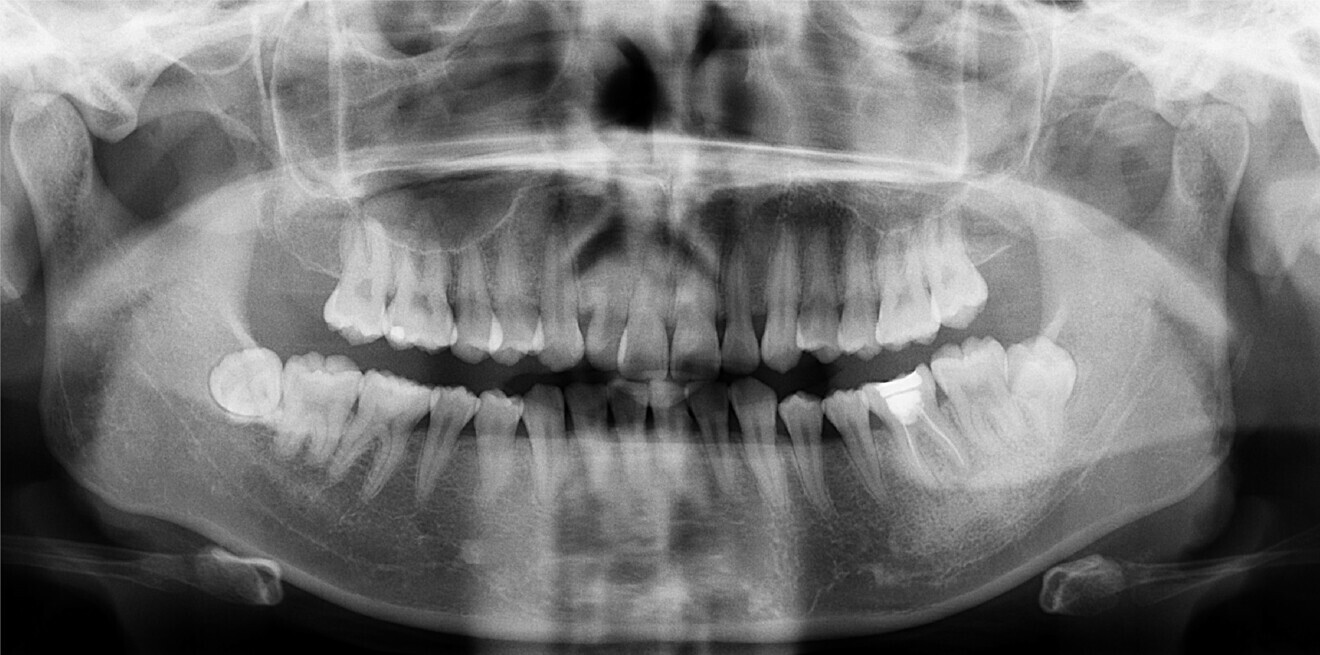

Fig. 2b: Dental panoramic tomogram taken before treatment began.